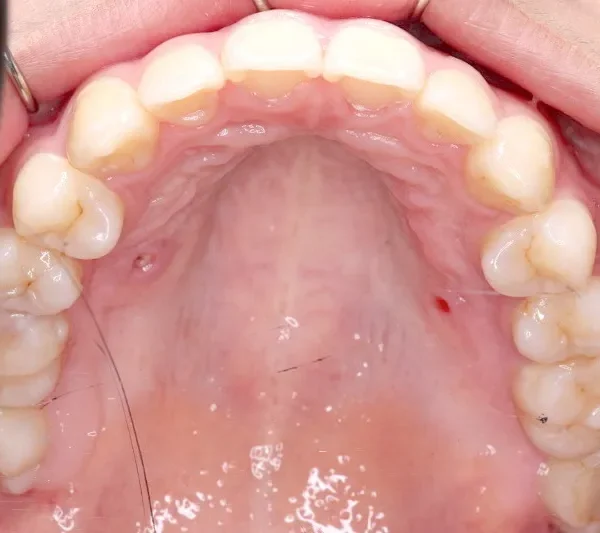

治療終了後

上下前から見える装置をつけ治療しました。歯は抜いてないです。

治療回数57回、6年9ヶ月の治療期間で矯正治療を終了しました。

主訴が改善され、ご満足頂きました。